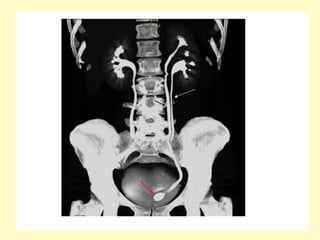

Renal agenesis, Coronal maximum intensity projection (a) and volume

rendering (b) demonstrate absence of the left kidney and

compensatory hypertrophy of the right kidney, which shows a

cortical cyst, the left main renal artery was absent